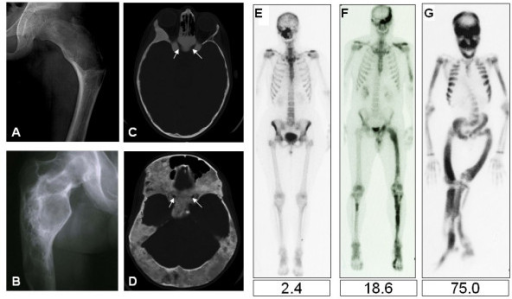

AP radiograph of the proximal femur demonstrating monostotic fibrous dysplasia. The lesion shows characteristic 'ground-glass' or 'smoky' appearance due to fibrous tissue with immature bone. There is expansion of the proximal femur with the classic 'shepherd's crook' deformity (coxa vara). The lesion has well-defined margins with no periosteal reaction. This is the most common location for symptomatic monostotic fibrous dysplasia.